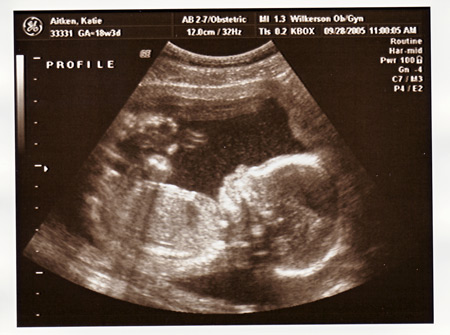

Here is Maeve's sonogram, from when she was the same gestational age: